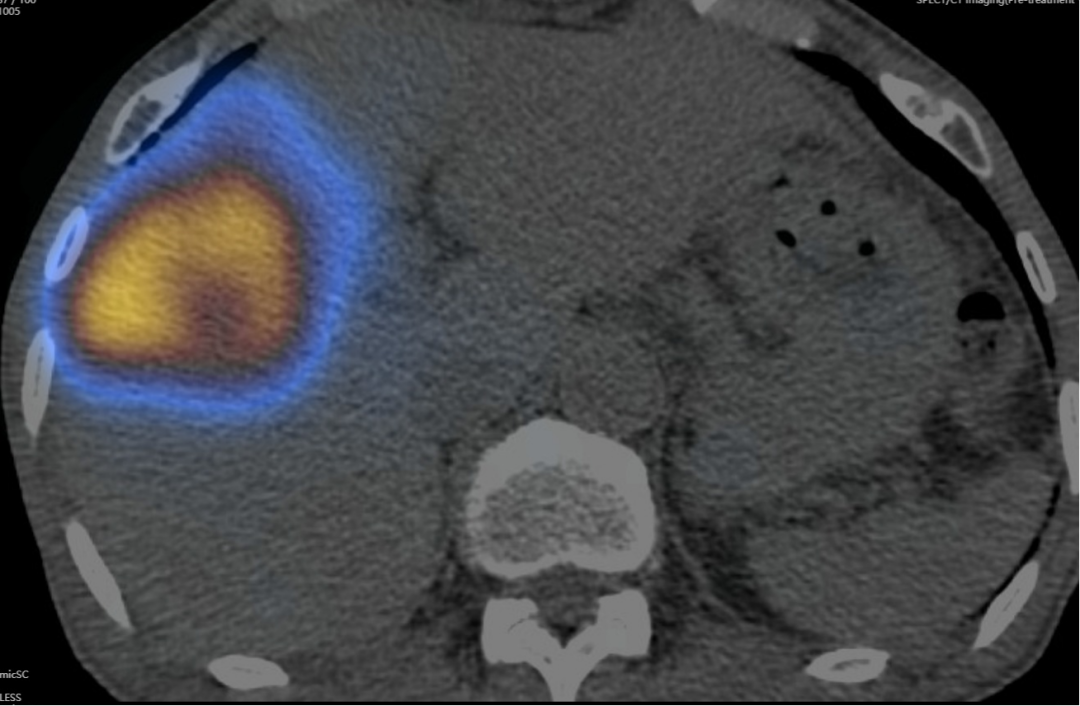

患者术后SPECT/CT显像,核素在病灶区沉积良好

由疾控感控办公室协助,全面做好接诊空间、疫情防控和消杀部署,核医学科、放射科、钇[90Y]中心导管室、留观室、肝胆胰中心医护团队严密防护,经约4小时,患者钇[90Y]微球介入治疗手术顺利完成。术后SPECT/CT显示病灶部位微球浓聚良好,无肝外微球异常浓聚,患者肝功正常,术后第二日顺利出院。